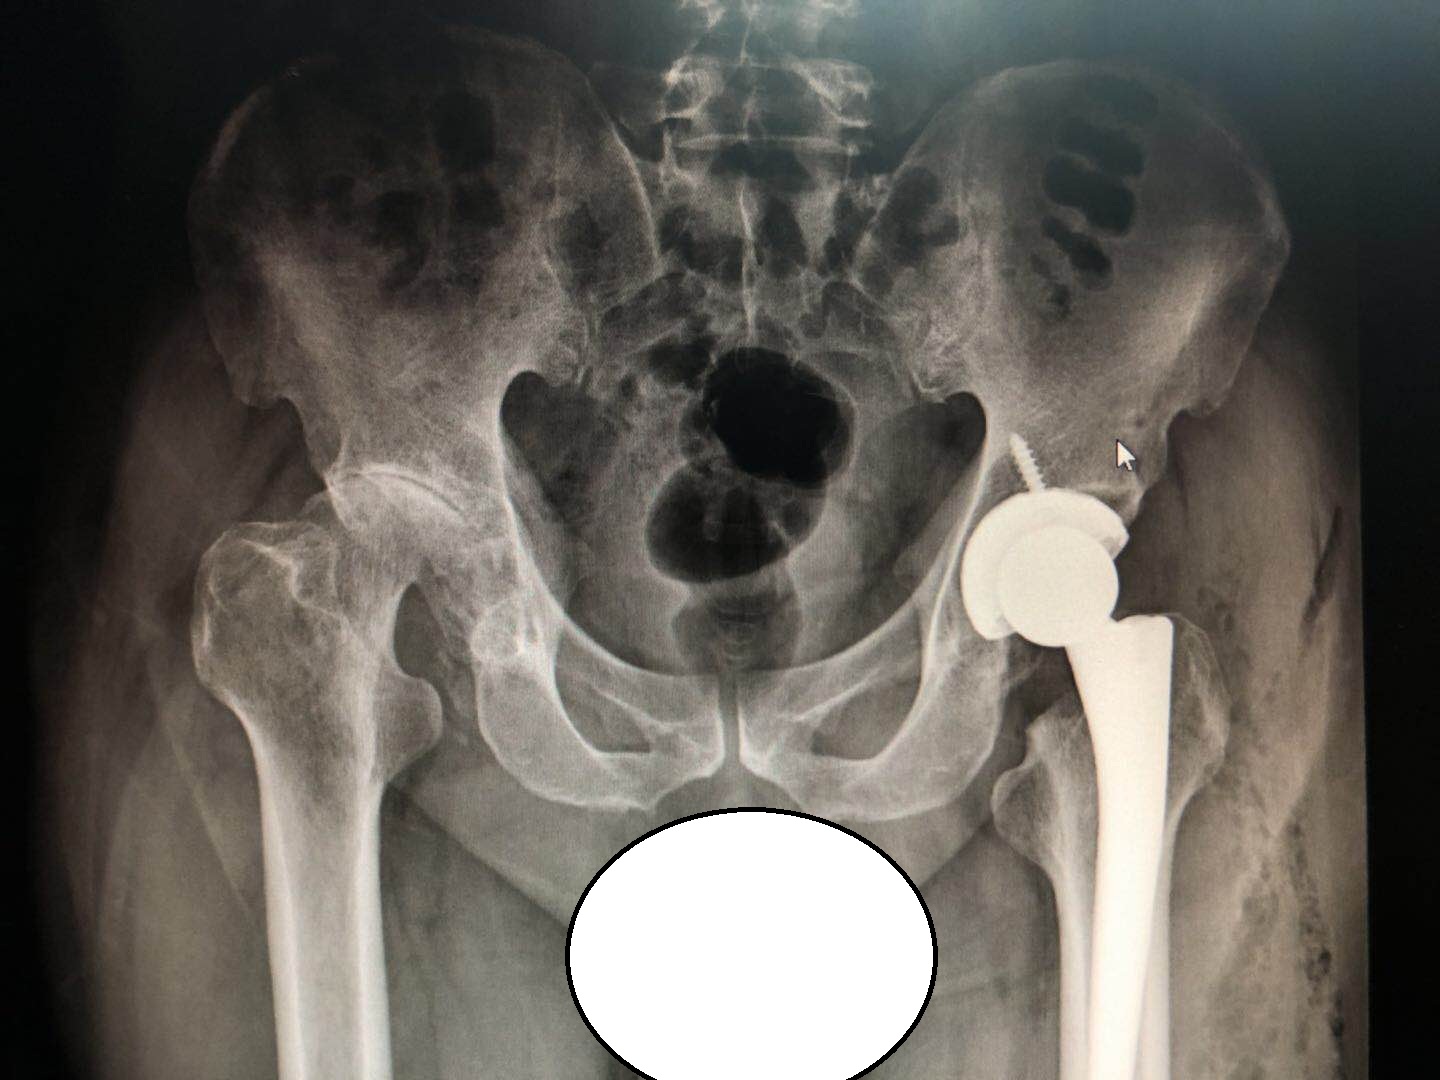

后面老陈在关节骨科及脊柱骨科医生们共同的讨论下,把症状最严重的左侧髋关节给换了,因为年纪不小了,两边一起做风险太大了......

老陈术后恢复很快,左边膝盖的疼痛已经明显好转,后面可能还要来做另外一边!